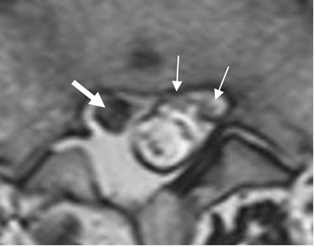

Fig 111. Retracción.

RM axial en T2. Laminectomía derecha, con fibrosis y retracción del saco dural y las raíces hacia la izquierda. (Flechas delgadas). Se aprecia engrosamiento de la raíz derecha. (Flecha gruesa).